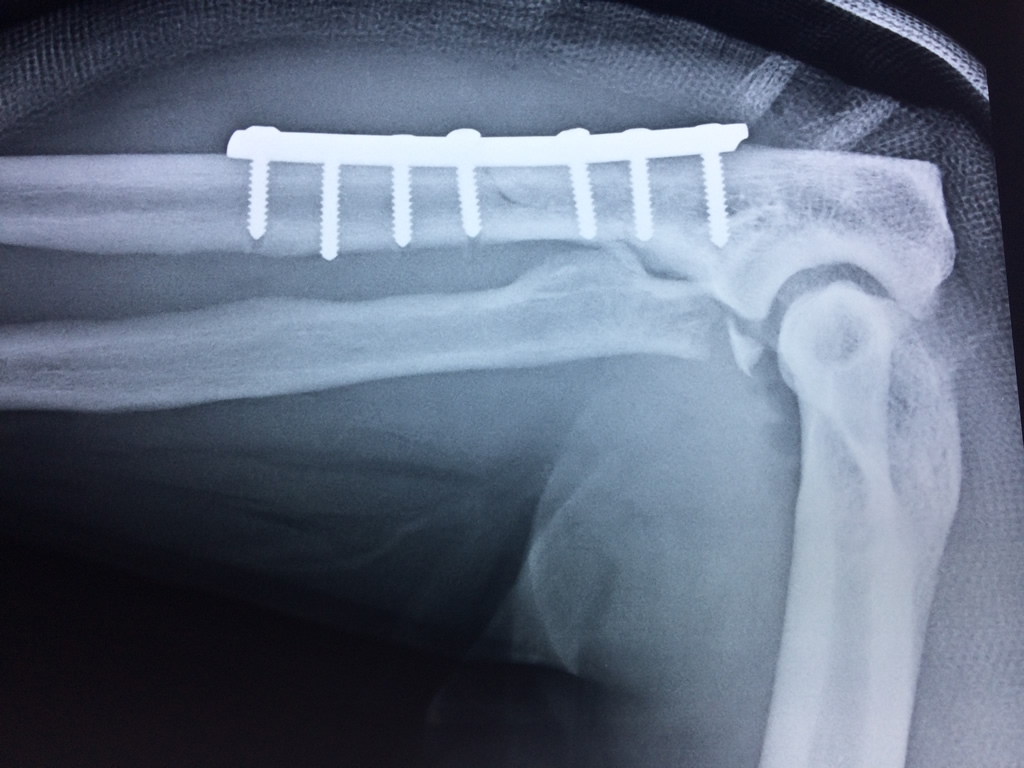

En el lenguaje común se le da el nombre de codo a la parte posterior y prominente situada en la unión del brazo con el antebrazo.